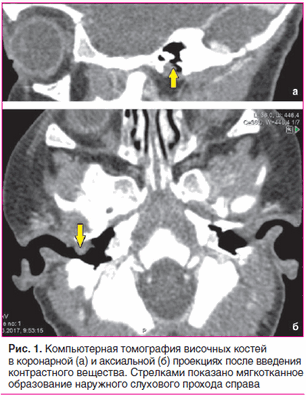

По данным компьютерной томографии височных костей, выполненной по стандартной программе до и после внутривенного введения контрастного вещества, на задней стенке наружного слухового прохода справа определяется мягкотканное образование однородной структуры, овальной формы с четкими контурами, размером 7×5,5 мм. Образование прилежит к барабанной перепонке, несколько смещает ее внутрь, умеренно накапливает контрастный препарат. Просвет наружного слухового прохода в данной области сужен до 1 мм. Костных деструктивных изменений не выявлено. Антрум и барабанные полости с обеих сторон пневматизированы. Слуховые косточки прослеживаются четко. Улитки без особенностей (рис. 1).